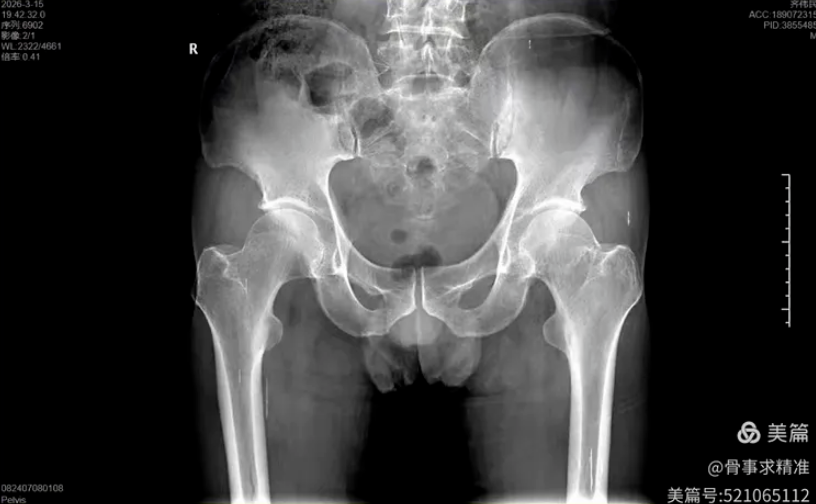

在全髋关节置换中,机器人实现髋臼磨挫深度、角度、臼杯前倾角、外展角完全量化,置钉方向与深度实时可视监测。尤其在DDH发育不良、髋关节翻修等解剖变异复杂病例中,精准导航能够降低手术风险,提高假体稳定性与长期生存率。

髋关节术后片